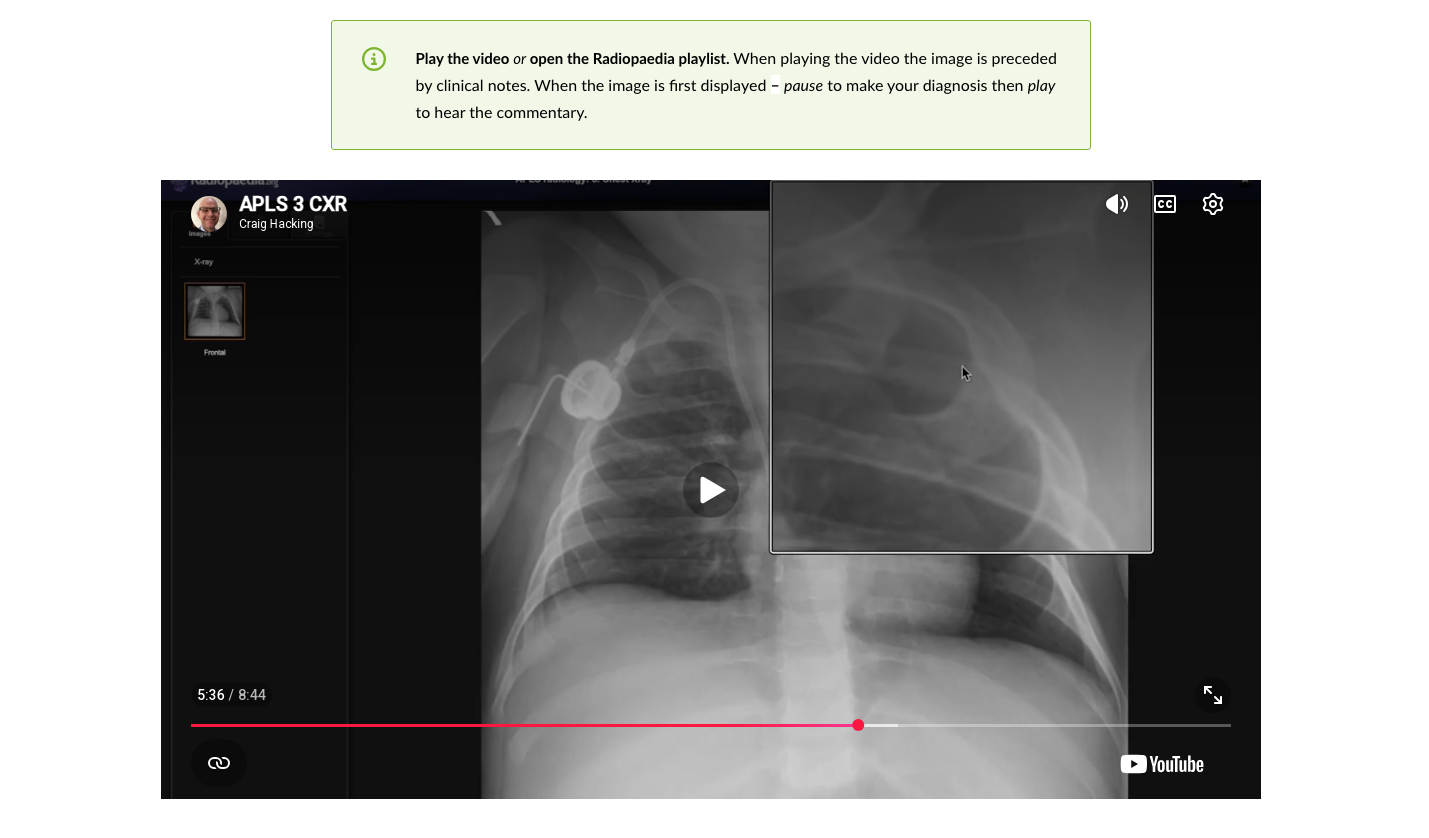

1. A major addition to the pre-course e-learning package in the form of an online workshop on Radiology, produced in collaboration with Radiopaedia